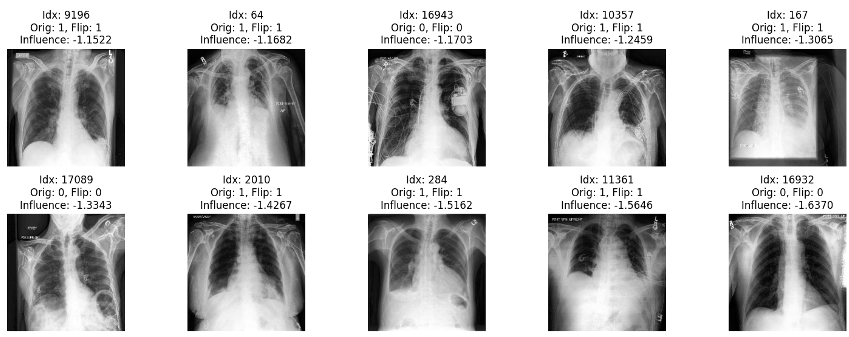

We also visualize the top 10 most harmful and helpful training samples for a given misclassified test sample. Examples for MNIST and CheXpert are shown in Fig. 4 and 5, respectively.

CheXpert

As shown in Fig. 5, only three out of the ten most harmful training points come from the flipped label distribution. However, considering that only 20% of training samples are flipped, the fact that flipped samples appear among the most harmful more frequently than random chance would suggest is still significant. In addition, the harmful training samples include some scans with unusual characteristics, such as odd patterns or artifacts.